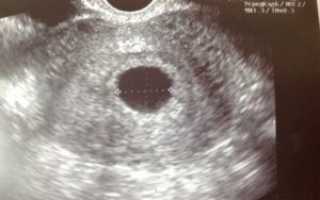

Во время ультразвукового исследования врач может обнаружить замершую беременность. Этот метод считается «золотым» стандартом при диагностике данной патологии. Отсутствие сердцебиений и отставание плода в размерах – главные симптомы замершей беременности при УЗИ.

• УЗИ: покажет прекращение сердцебиения плода. Не паникуйте раньше времени, если врач не услышал сердцебиение плода через стетоскоп — такое возможно при переднем расположении плаценты или наличии жировой прослойки на брюшной стенке;

Если при ультразвуковом исследовании диагностирована замершая беременность, видео «показывает» отсутствие сердцебиения у плода.